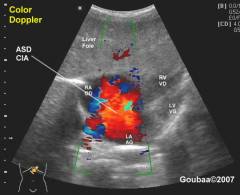

УЗИ сердца с допплеровским исследованием

Исследование сердца с использованием ультразвука. Позволяет выявить особенности кровотока через дефект.

При ДМЖП видны:

- Отверстие в перегородке;

- Размер и расположение дефекта;

- Красным цветом отображается поток крови к датчику, синим – в противоположном направлении.

Исследование сердца с использованием ультразвука. На основе отраженных ультразвуковых волн создается изображение сердца в реальном времени. Методика позволяет выявить особенности кровотока через дефект.

При наличии ДМЖП можно увидеть:

- отверстие в перегородке между желудочками;

- его размеры и расположение;

- красным цветом отображается поток крови, движущийся к датчику, синим – в противоположном направлении. Чем ярче оттенок, тем выше скорость кровотока и давление в желудочках.